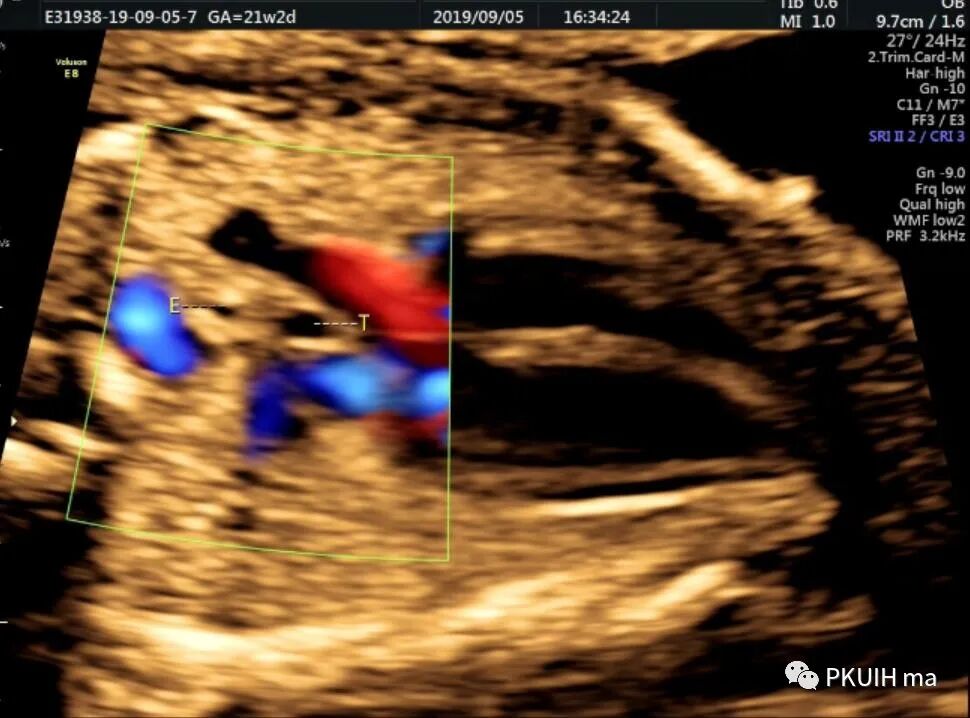

脊柱前方一红色血管为迷走的右锁骨下动脉,频谱为动脉频谱

冠状切面显示右锁骨下动脉起于主动脉弓降部(ARSA:迷走的右锁骨下动脉,LSA:左锁骨下动脉)